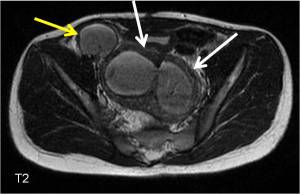

History: 13 year old female with pelvic pain

This is a case of a bicornuate uterus with hydrosalpinx of the right fallopian tube. Read about Imaging of Mullerian Duct Anomalies.